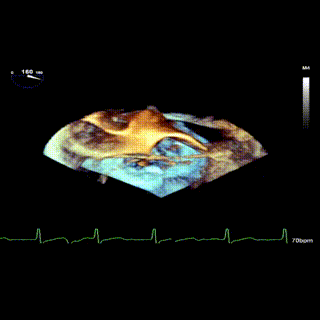

3D

怎么上穿刺鞘攻克巨大左房伴转位穿刺难关!温医大附一院周浩教授团队创新应用“导丝定位+可调弯鞘”技术完成高难度TEER手术_https://www.jmylbn.com_新闻资讯_第9张

3D带彩